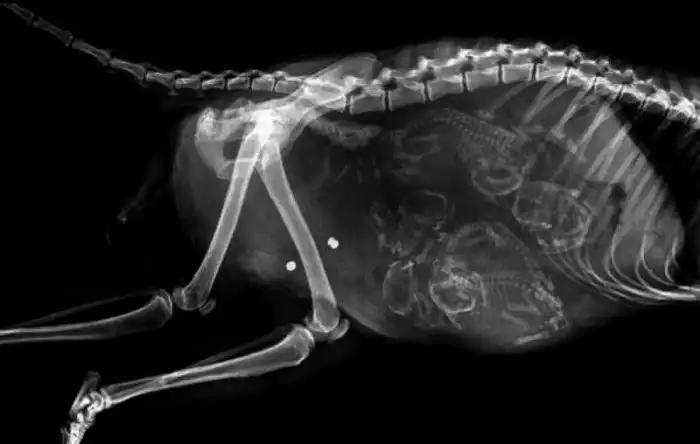

Специалисты, которые по долгу своей работы наблюдают животных, готовых принести потомство, поделились этими удивительными рентгеновскими и ультразвуковыми снимками.

3. Беременная кошка